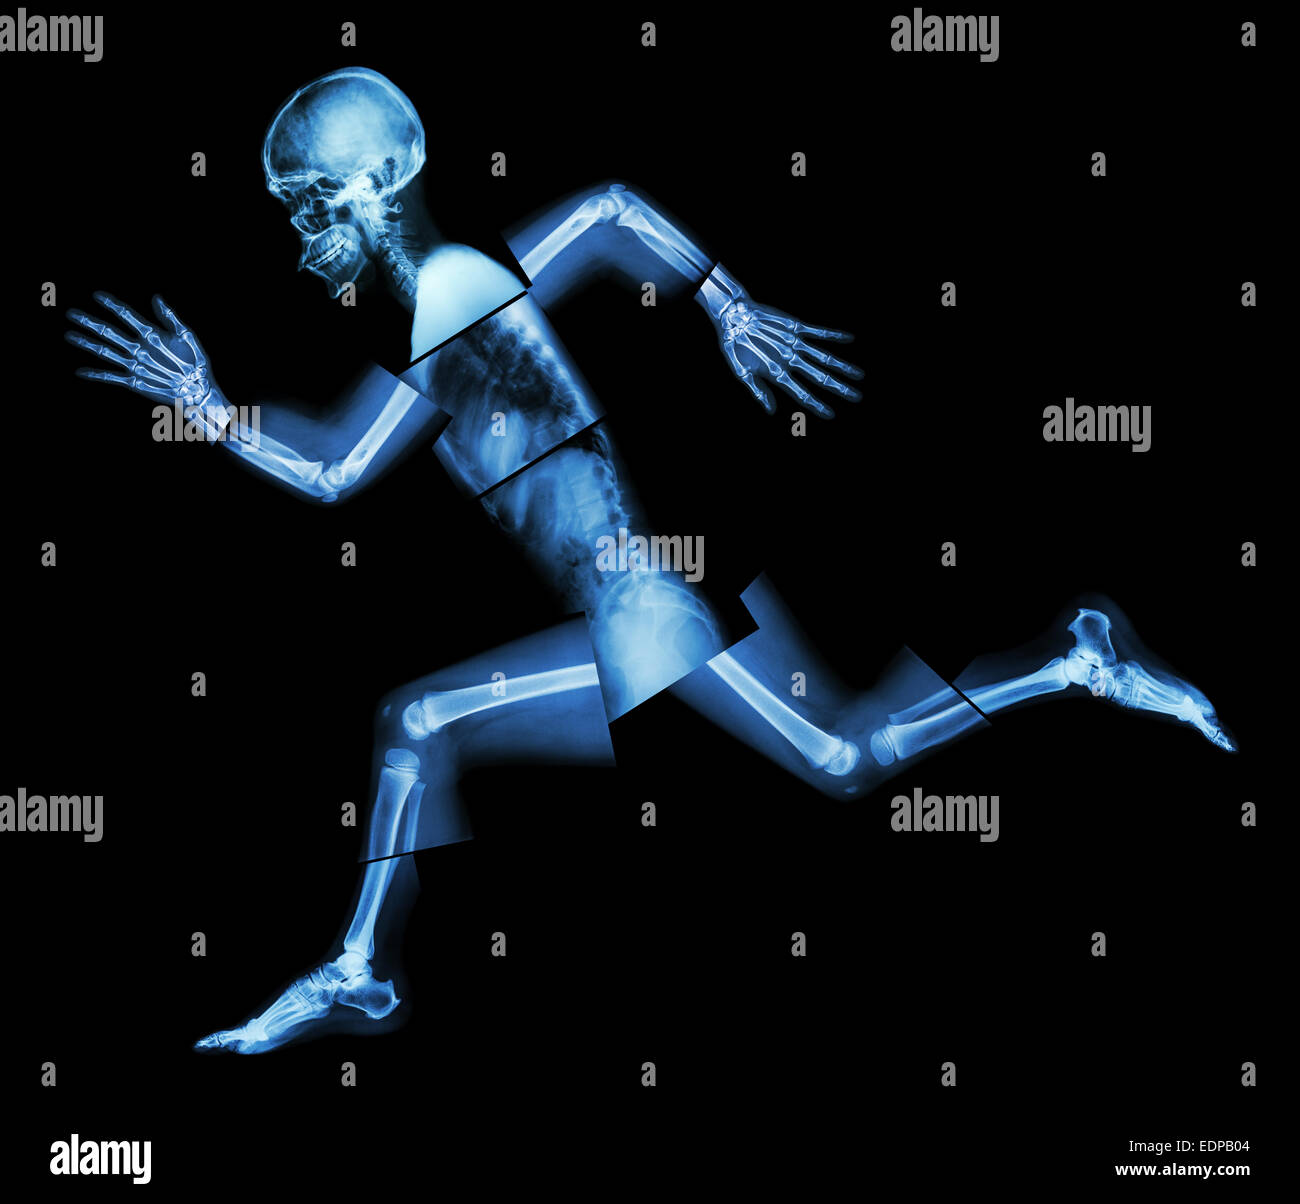

Marathon (les droits de l'os est en marche) ,(corps entier x-ray : tête, cou, bras, épaule, coude, avant-bras, main, doigt ,,commune thorax ,ab Banque D'Imageshttps://www.alamyimages.fr/image-license-details/?v=1https://www.alamyimages.fr/photo-image-marathon-les-droits-de-l-os-est-en-marche-corps-entier-x-ray-tete-cou-bras-epaule-coude-avant-bras-main-doigt-commune-thorax-ab-77324375.html

Marathon (les droits de l'os est en marche) ,(corps entier x-ray : tête, cou, bras, épaule, coude, avant-bras, main, doigt ,,commune thorax ,ab Banque D'Imageshttps://www.alamyimages.fr/image-license-details/?v=1https://www.alamyimages.fr/photo-image-marathon-les-droits-de-l-os-est-en-marche-corps-entier-x-ray-tete-cou-bras-epaule-coude-avant-bras-main-doigt-commune-thorax-ab-77324375.htmlRFEDPC0R–Marathon (les droits de l'os est en marche) ,(corps entier x-ray : tête, cou, bras, épaule, coude, avant-bras, main, doigt ,,commune thorax ,ab

Marathon (les droits de l'os est en marche) ,(corps entier x-ray : tête, cou, bras, épaule, coude, avant-bras, main, doigt ,,commune thorax ,ab Banque D'Imageshttps://www.alamyimages.fr/image-license-details/?v=1https://www.alamyimages.fr/photo-image-marathon-les-droits-de-l-os-est-en-marche-corps-entier-x-ray-tete-cou-bras-epaule-coude-avant-bras-main-doigt-commune-thorax-ab-77324374.html

Marathon (les droits de l'os est en marche) ,(corps entier x-ray : tête, cou, bras, épaule, coude, avant-bras, main, doigt ,,commune thorax ,ab Banque D'Imageshttps://www.alamyimages.fr/image-license-details/?v=1https://www.alamyimages.fr/photo-image-marathon-les-droits-de-l-os-est-en-marche-corps-entier-x-ray-tete-cou-bras-epaule-coude-avant-bras-main-doigt-commune-thorax-ab-77324374.htmlRFEDPC0P–Marathon (les droits de l'os est en marche) ,(corps entier x-ray : tête, cou, bras, épaule, coude, avant-bras, main, doigt ,,commune thorax ,ab

Marathon (les droits de l'os est en marche) ,(corps entier x-ray : tête, cou, bras, épaule, coude, avant-bras, main, doigt ,,commune thorax ,ab Banque D'Imageshttps://www.alamyimages.fr/image-license-details/?v=1https://www.alamyimages.fr/photo-image-marathon-les-droits-de-l-os-est-en-marche-corps-entier-x-ray-tete-cou-bras-epaule-coude-avant-bras-main-doigt-commune-thorax-ab-77323572.html

Marathon (les droits de l'os est en marche) ,(corps entier x-ray : tête, cou, bras, épaule, coude, avant-bras, main, doigt ,,commune thorax ,ab Banque D'Imageshttps://www.alamyimages.fr/image-license-details/?v=1https://www.alamyimages.fr/photo-image-marathon-les-droits-de-l-os-est-en-marche-corps-entier-x-ray-tete-cou-bras-epaule-coude-avant-bras-main-doigt-commune-thorax-ab-77323572.htmlRFEDPB04–Marathon (les droits de l'os est en marche) ,(corps entier x-ray : tête, cou, bras, épaule, coude, avant-bras, main, doigt ,,commune thorax ,ab

Marathon (les droits de l'os est en marche) ,(corps entier x-ray : tête, cou, bras, épaule, coude, avant-bras, main, doigt ,,commune thorax ,ab Banque D'Imageshttps://www.alamyimages.fr/image-license-details/?v=1https://www.alamyimages.fr/photo-image-marathon-les-droits-de-l-os-est-en-marche-corps-entier-x-ray-tete-cou-bras-epaule-coude-avant-bras-main-doigt-commune-thorax-ab-77324380.html

Marathon (les droits de l'os est en marche) ,(corps entier x-ray : tête, cou, bras, épaule, coude, avant-bras, main, doigt ,,commune thorax ,ab Banque D'Imageshttps://www.alamyimages.fr/image-license-details/?v=1https://www.alamyimages.fr/photo-image-marathon-les-droits-de-l-os-est-en-marche-corps-entier-x-ray-tete-cou-bras-epaule-coude-avant-bras-main-doigt-commune-thorax-ab-77324380.htmlRFEDPC10–Marathon (les droits de l'os est en marche) ,(corps entier x-ray : tête, cou, bras, épaule, coude, avant-bras, main, doigt ,,commune thorax ,ab